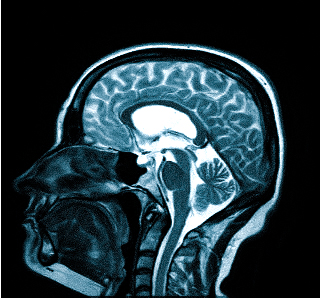

Боль при шейном остеохондрозе изначально возникает в затылке, а по мере прогрессирования патологии распространяется на лобно-височную область головы

Болевой синдром при различных патологиях имеет разную интенсивность, локализацию, длительность и может сопровождаться рядом других неприятных симптомов: тошнотой, выпадением полей зрения, потерей сознания и пр. Цефалгия развивается самостоятельно или сопутствует какому-либо состоянию. Специалисты едины во мнении: если регулярно беспокоит ноющая, мигренеподобная, распирающая и другая головная боль в темечке, затылке, висках, следует обратиться на очную консультацию и пройти первичную диагностику:

Врач определяет не только вид обследования, но и его объем. Иногда требуется дать оценку не только структурам мозга, но и воротниковой зоны: голова может кружиться и болеть при шейном остеохондрозе, грыже, воспалении нерва и пр.